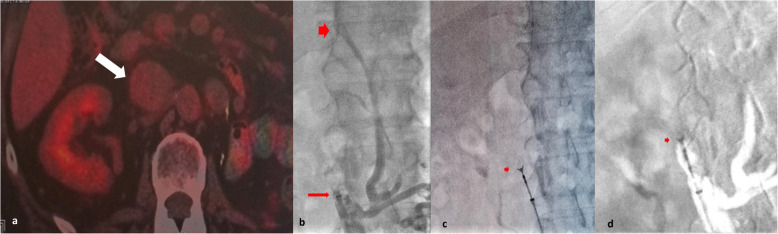

Endovascular inferior vena cava (IVC) mass biopsy emerges as a minimally invasive promising technique for the acquisition of tissue samples for histological analysis, crucial for determining the malignant or benign nature of the lesion and guiding subsequent treatment. This report details the first successful off label use of a low-profile 5.2Fr biliary forceps system, via a 7Fr sheath, for endovascular IVC biopsy in a 61-year-old male patient with a history of left nephrectomy due to Gravitz tumour presenting with IVC thrombosis at 5-years follow up, suspicious for recurrence.